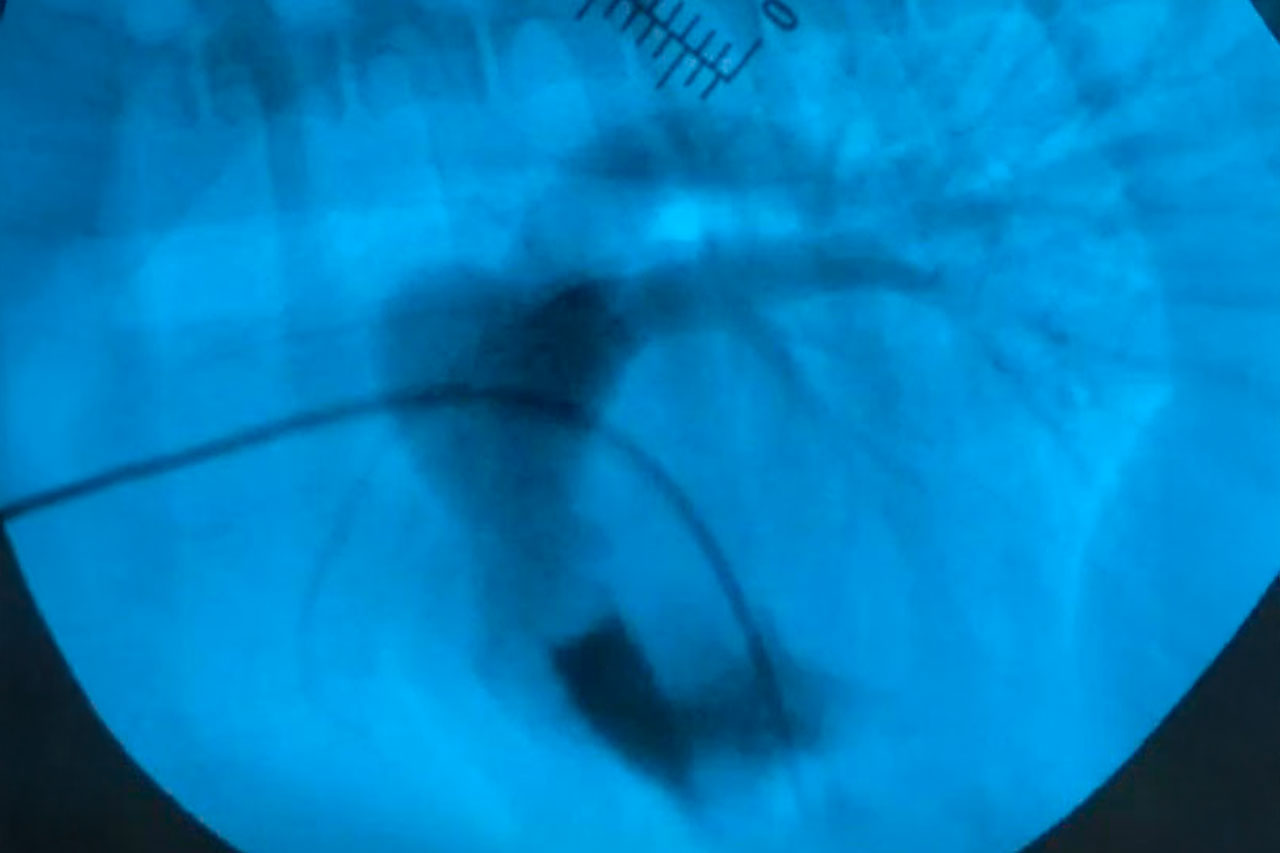

Die Behandlung einer Pulmonalstenose hängt von dem Schweregrad der Erkrankung ab. In milden Fällen ist möglicherweise keine sofortige Behandlung erforderlich, jedoch sind regelmäßige Kontrollen ratsam. Bei schwereren Fällen steht die Option des Eingriffes zur Verfügung: Ballonvalvuloplastie. Bei dieser minimal-invasiven Technik wird ein Ballon eingesetzt, um die verengte Klappe zu erweitern.

Impressionen zur Ballonvalvuloplastie